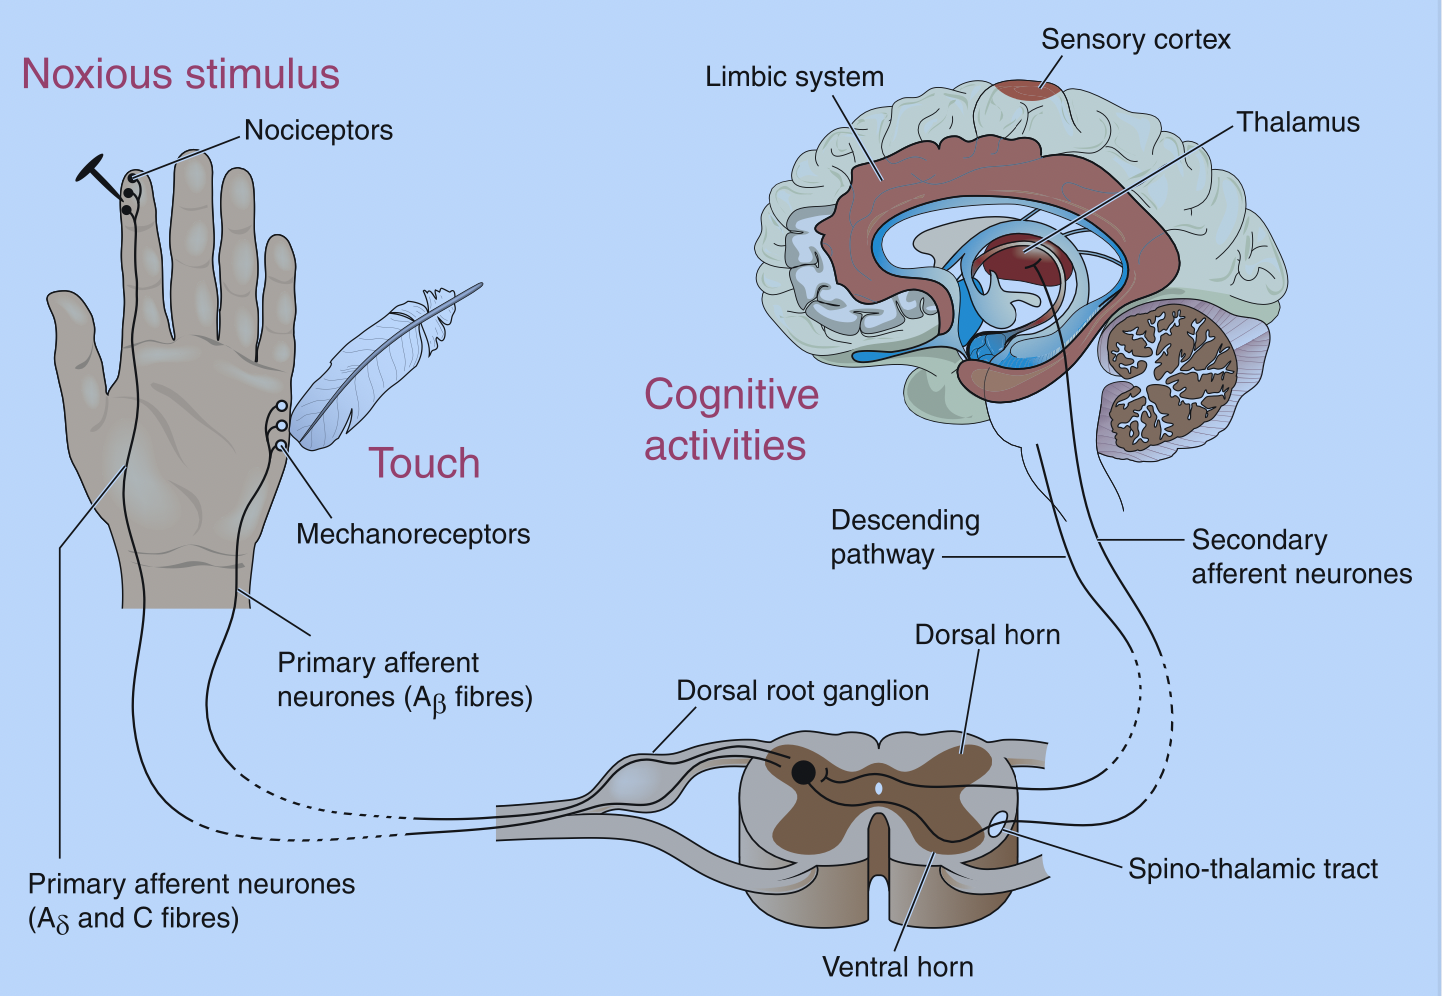

手外伤患者发生复杂区域疼痛综合征 (CRPS) 的危险因素

参加手部治疗的患者的手部创伤和 CRPS 作者:Tristany Hightower Savaş, S., Ánal, EE, Yavuz, DD, Uslusoy, F., Altuntaş, SH, ...

手部治疗中周围神经修复后的镜像疗法

快速回顾 Paula, MH、Barbosa, RI、Marcolino, AM、Elui, VM、Rosén, B. 和 Fonseca, MC (2016)。早期感觉再教育...